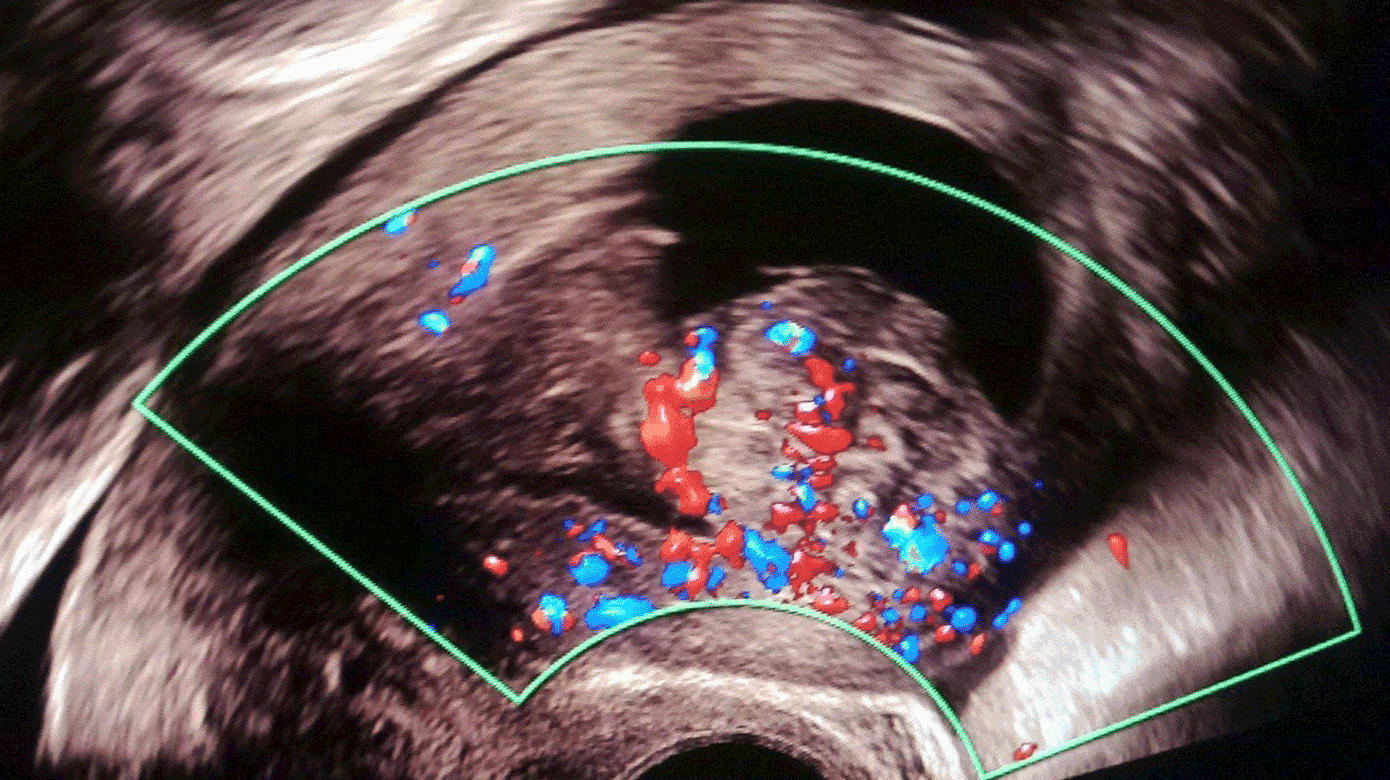

Ved stuegang seks timer senere sås fortsat pågående blødning, som blev estimeret til 600 ml på lejet. Transvaginal ultralydskanning viste moderat flow i den intrakavitære process (Figur 1) og det underliggende myometrium. Rigeligt flow i kombination med kraftig blødning rejste mistanke om sarkom. Man konfererede med onkogynækolog på højtspecialiseret sygehus, som anbefalede at undgå hysteroskopi. Hgb = 4,0 mmol/l efter i alt fem portioner SAG-M, men rotationel tromboelastometri var normal, og der var således ikke længere tale om medicinsk blødning. Der blev givet yderligere to portioner SAG-M og en portion trombocytter. Man forberedte at anlægge en komprimerende ballon i uterus. Patienten blev informeret om, at der ved ukontrollabel blødning var risiko for, at man måtte foretage hysterektomi. Da patienten ikke samtykkede til hysterektomi og på det tidspunkt var transportabel med lægefølge, blev det i samråd med højtspecialiseret sygehus besluttet at udføre akut CT-angiografi og overflytning med henblik på embolisering.